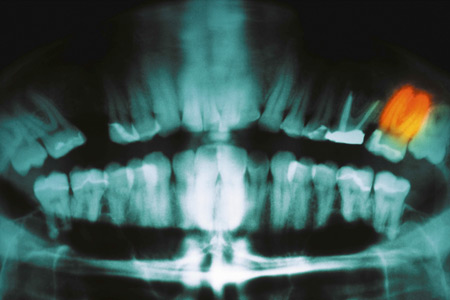

Wissenschaftler des Suncoast University Medical Center in Panama haben ein Verfahren entwickelt, das es künftig ermöglichen soll, abgebrochene oder kariöse Zähne wieder wachsen zu lassen. Dem Team um Wil Smith ist es gelungen, mithilfe von Stammzellen bei Schweinen die Oberkiefer Frontzähne zu erneuern.

Damit konnte erstmals die vollständige Oberfläche eines Zahns sowie die Funktionsfähigkeit wieder hergestellt werden, ohne dass mechanisch nachgeholfen werden musste. Profitieren sollen vor allem Patienten, bei denen aufgrund eines Unfalls Zähne beschädigt wurden sowie Patienten mit schwerer Karies.

Die Wissenschaftler entfernten bei zehn Schweinen die beiden Oberkiefer Frontzähne und ersetzten sie mit einem speziellen Provisorium, welches sich mit der Zeit selbst auflöst. Dieses Provisorium wurde mit Chemikalien versehen, welche Stammzellen anziehen, die Zähne bilden können. Nach vier Wochen verfügten die Tiere wieder über eigene Frontzähne und konnten ganz normal Nahrung aufnehmen.